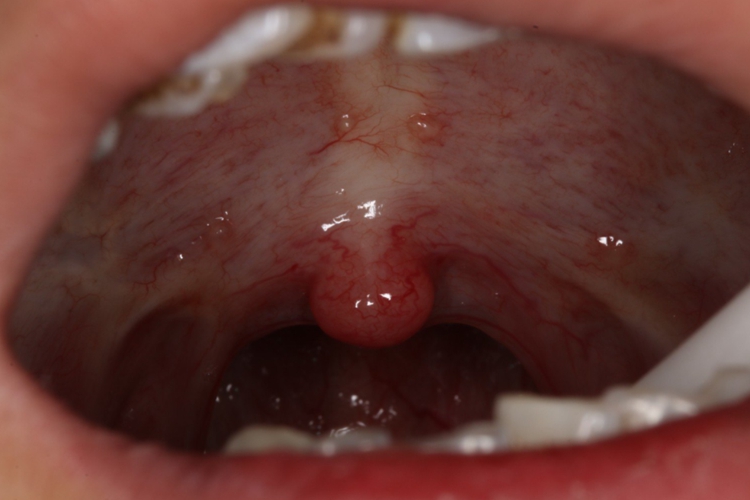

复发性口疮:吃槟榔导致复发性口疮,口腔黏膜部位的病损为溃疡,会出现黏膜充血性红斑,然后会有不断向四周扩展的溃疡面,呈圆形或椭圆形,可以出现多个大小不等、深浅不一的溃疡面。

接触性口炎:患者吃槟榔后口腔黏膜局部会出现水疱、糜烂或溃疡,甚至有组织坏死,表面渗出形成假膜覆盖。溃烂面除可发生在接触部位外,还可以向邻近部位扩展,患者会有明显的灼热、刺痛感。

口腔黏膜下纤维性变:患者吃槟榔后口腔黏膜有灼痛感,会逐渐形成苍白或灰白色糜烂面,部分患者软腭上会有水疱及破溃,口腔黏膜会发白并伴有皮革样的质地改变,同时会伴有口干、味觉丧失、张口受限等不适症状。